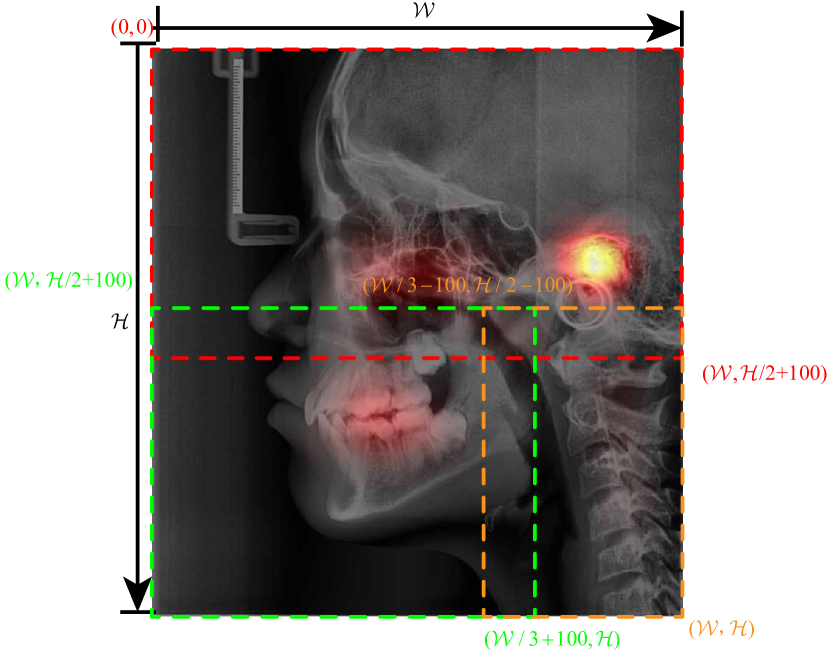

where is the mean saliency map of age , , is the count of samples with age in training set, , is the saliency map of sample and means element-wise summation. As the mean saliency map shown in 11, we can find that the more significant parts in the LC image are mainly concentrated in three parts. Each LC image was divided into these three overlapping parts with the same strategy, because when the LC image is imaged, the position and posture of the subject relative to the shooting device are almost fixed. As shown in Fig. 3, for a specific LC image, set its width and height as and respectively, let the upper left corner of the LC image as the origin of the coordinates, right and down as the positive direction of the x-axis and y-axis, and the width of one pixel as the unit length, establish a coordinate system, the coordinates of the upper left and lower right corners of the rectangle of the skull are and respectively. If the orientation is left, the coordinates of the upper left and lower right corners of the rectangle of the tooth part are , , the upper left and lower right corners of the rectangle of the spine part The coordinates are , ; If the orientation is right, each part is mirror-symmetrical to those of the image facing the left.

In order to compare their performance in the age estimation and provide guidance for forensic practice, each part of the sample was used as the input of the model. In order to analyze the contribution of each region in the local image to the age estimation more accurately and verify the reliability of the saliency area of the saliency map of the entire image, the saliency maps of each local image were also generated.

In order to assess the contribution of each salient part in the LC image, we divided the LC image into three parts as shown in Fig. 3. A, B, and C part of LC image were used as the input of the network respectively to assess the performance of every single part for age estimation. After that, the A, B, and C parts of the LC image were combined in pairs as the input of network to assess the performance of age estimation when each area of the LC image is missing. The split of data set, training parameters and network remain unchanged.